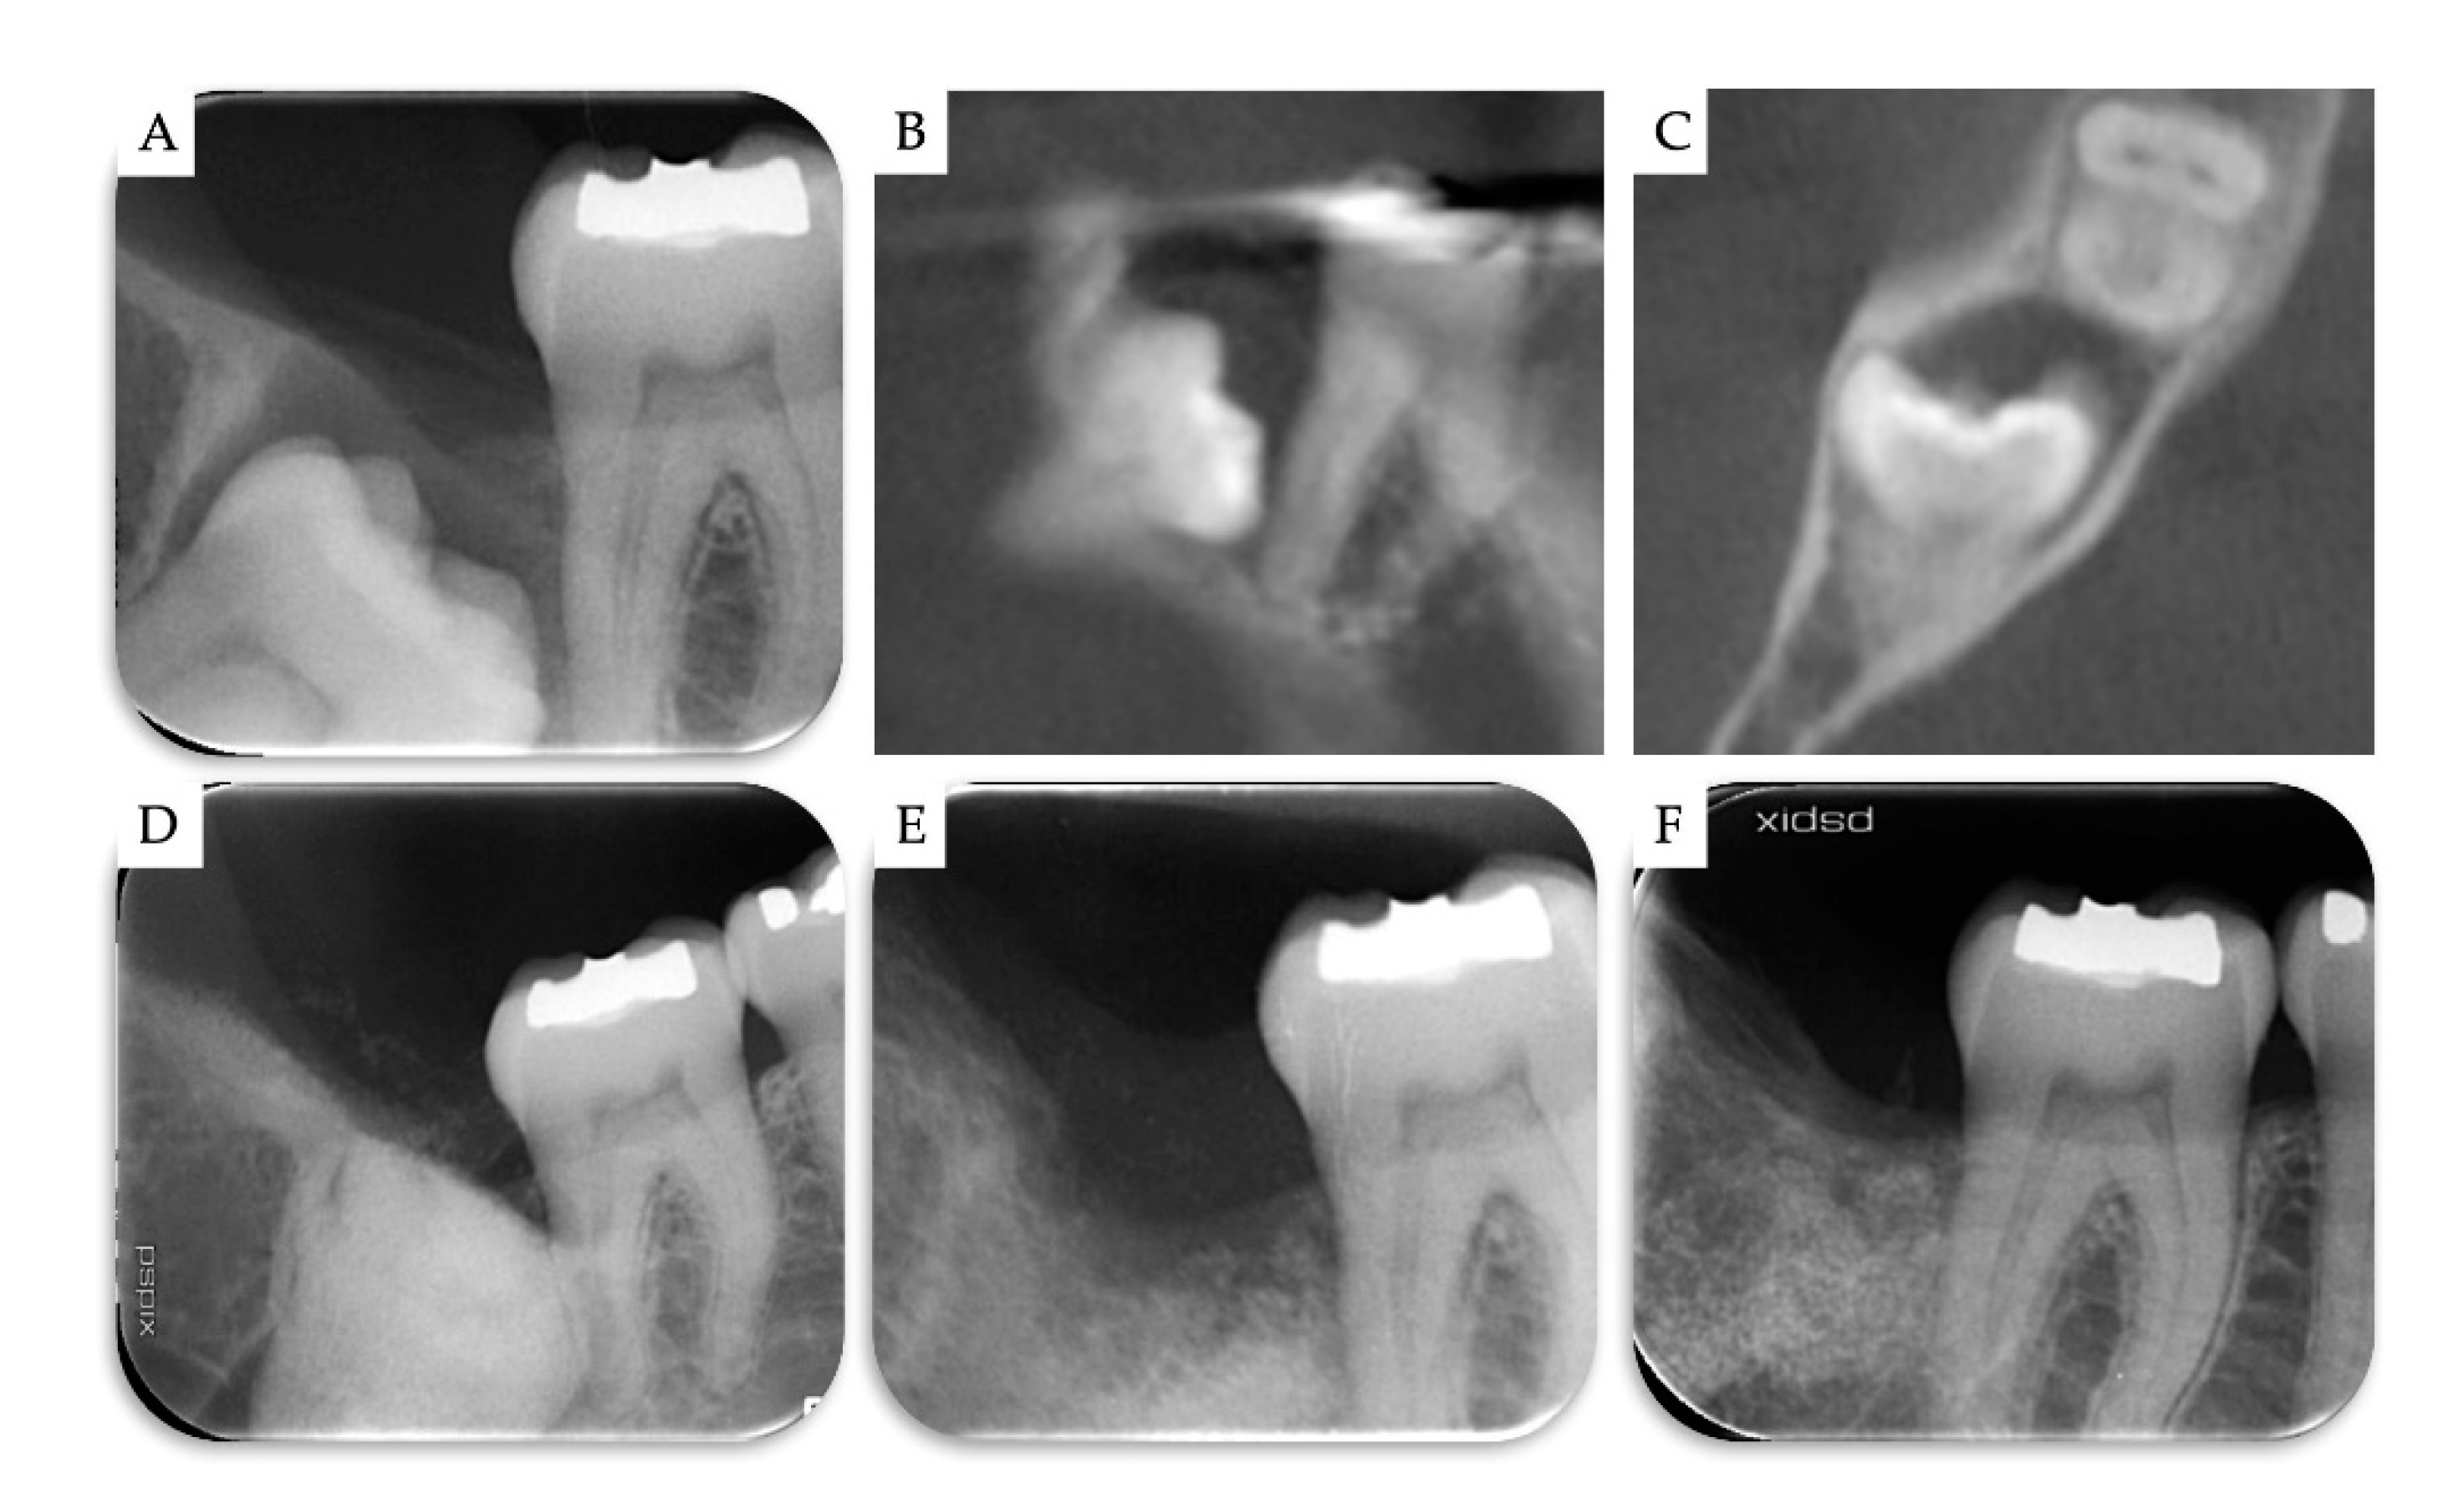

3. Results

| Case | Gender | Age | Smoker | M3 | Impaction | Follow-Up (years) | PD T0 (mm) | PD T1 (mm) | BD T0 (mm) | BD T1 (mm) | BG (mm) |

|---|---|---|---|---|---|---|---|---|---|---|---|

| 1 | F | 51 | No | 48 | Mesio-angular | 2 | 12 | 3 | 11.1 | 5.2 | 5.86 |

| 2 | F | 36 | No | 38 | Horizontal | 2 | - | 1 | 7.4 | 1.3 | 6.1 |

| 3 | M | 42 | No | 38 | Horizontal | 1 | - | 2 | 10.2 | 4.4 | 5.79 |

| 4 | M | 34 | No | 48 | Horizontal | 1 | - | 2 | 8.6 | 2.1 | 6.51 |

| Mean | 40.75 | 1.5 | 2.00 | 9.33 | 3.25 | 6.07 | |||||

| SD | 6.61 | 0.5 | 0.71 | 1.43 | 1.6 | 0.28 |